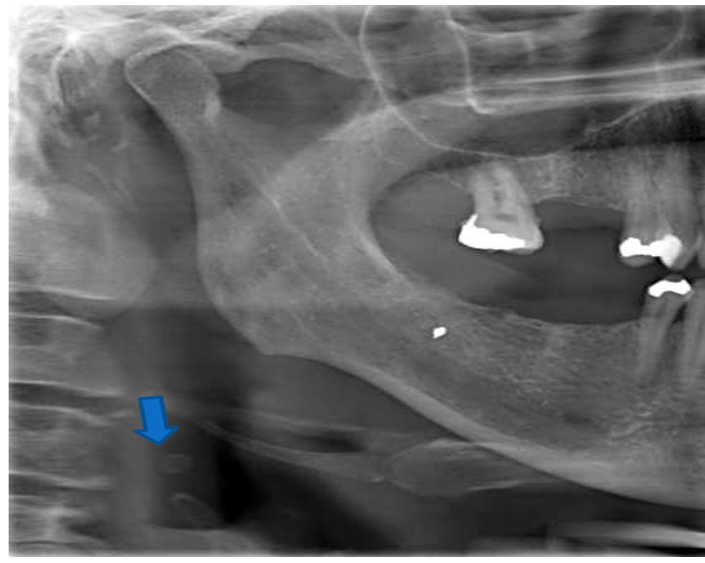

6) Identify the curved soft tissue radiopacity indicated by the blue arrow. Patient suffered from a road traffic accident and you see bilateral mandibular fractures.